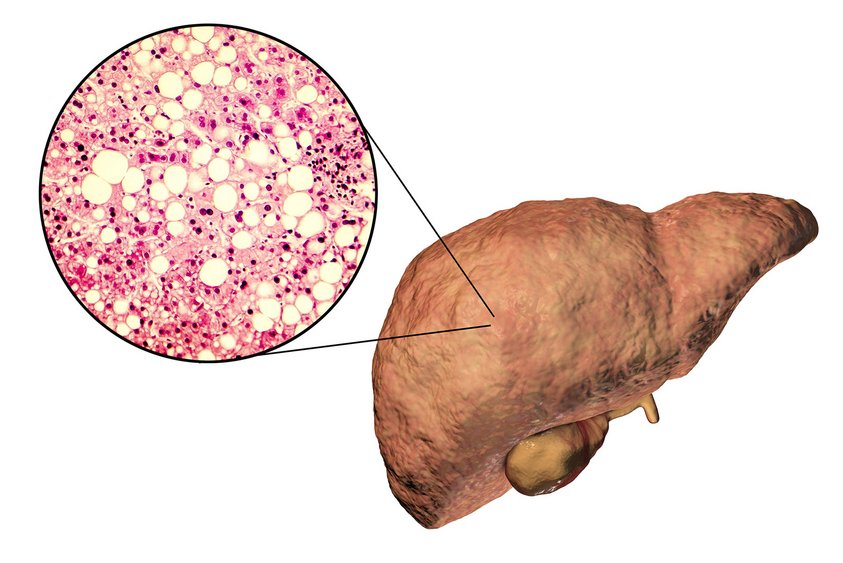

Die nichtalkoholische Fettlebererkrankung gehört in den wohlhabenderen Ländern mit den vielen Übergewichtigen zu einer der am meisten unterschätztesten Krankheiten. Im weiteren Verlauf führt dies oft zu einer Leberentzündung und im Endstadium dann zu einer Leberzirrhose.

Bei jedem Fünften mit Leberkrebs ist die Fettleber die Ursache und Leberentzündungen gehören heute zu den häufigsten Gründen für eine Lebertransplantation. Doch auch die Qualität der Spenderlebern sinkt. Schuld sind auch hierfür Fettlebern und Entzündungen der Leber.

Britische Wissenschaftler untersuchten rund 4.000 Studienteilnehmer seit ihrer Geburt in den Jahren 1991 und 1992. Die Probanden sind also inzwischen 27 bis 28 Jahre alt. In den Jahren 2015 und 2017 wurde bei ihnen die Leber untersucht, also im Alter von Mitte 20. In diesem Alter wiesen 20,7 Prozent der Untersuchten eine Fettleber auf und 2,7 Prozent eine Leberfibrose. Diese Zahlen entsprechen in etwa den Ergebnissen von US-amerikanischen Studien.